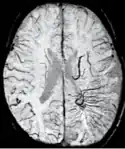

Comparison of diffuse axonal injury imaged with conventional GRE (left) and SWI (right) at 1.5 T

Comparison of hemorrhage imaged with conventional GRE (left) and SWI (right) at 1.5 T

The detection of micro-hemorrhages, shearing, and diffuse axonal injury (DAI) in trauma patients is often difficult as the injuries tend to be relatively small in size and can be easily missed by low resolution scans. SWI is usually run at relatively high resolution (1 mm3) and is extremely sensitive to bleeding in the gray matter/white matter boundaries making it is possible to see very small lesions increasing the ability to detect more subtle injuries.